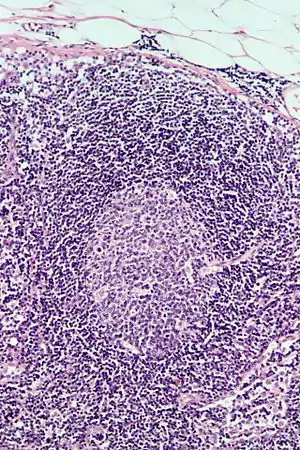

Follicular hyperplasia (FH) is a type of lymphoid hyperplasia and is classified as a lymphadenopathy, which means a disease of the lymph nodes. It is caused by a stimulation of the B cell compartment and by abnormal cell growth of secondary follicles. This typically occurs in the cortex without disrupting the lymph node capsule.[1] The follicles are pathologically polymorphous, are often contrasting and varying in size and shape.[2] Follicular hyperplasia is distinguished from follicular lymphoma in its polyclonality and lack of bcl-2 protein expression, whereas follicular lymphoma is monoclonal, and expresses bcl-2.[3]

Follicular hyperplasia can be distinguished among other diseases by observing the density of a lymph follicle on low magnification. Lymph nodes with reactive follicles contain extensions outside its capsule, follicles present throughout the entire node, obvious centroblasts and the absence or diminishing mantle zones. Immunohistochemistry can help distinguish a difference between a patient with follicular lymphoma to follicular hyperplasia.[1] Reactive follicular hyperplasia does not express BCL2 proteins in B cell germinal centers and are absent light chain reaction in immunostaining and flow cytometry as well as absent IG rearrangements.[1]

BCL2 protein expression is usually absent in follicular hyperplasia but prominent in follicular lymphomas. A comparison with other stains that include germinal center markers such as BCL-6 or CD10 is useful to compare when determining a proper diagnosis.[1] CD10 positive cells are metalloproteinase which activate or deactivate peptides through proteolytic cleavage.[10]